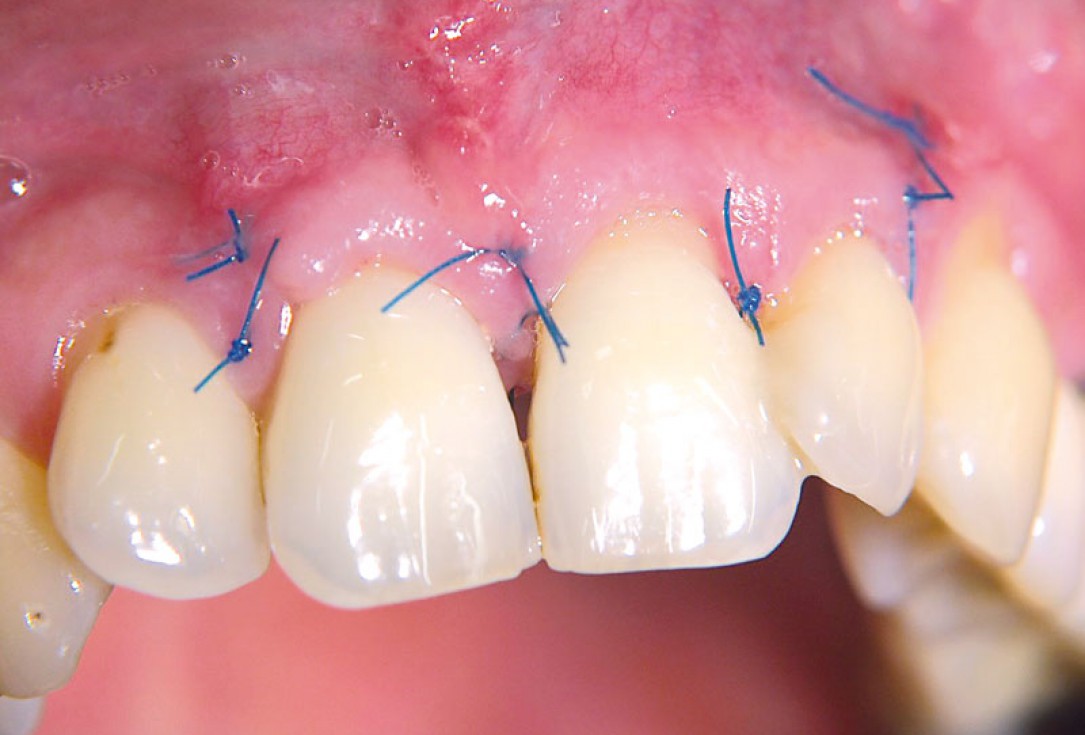

10/11 - Clinical situation 3 weeks post-surgical.Non-contained intrabony defect treated using cerabone®, collprotect® membrane and Straumann® Emdogain® - Dr. T. Schwaar (2)